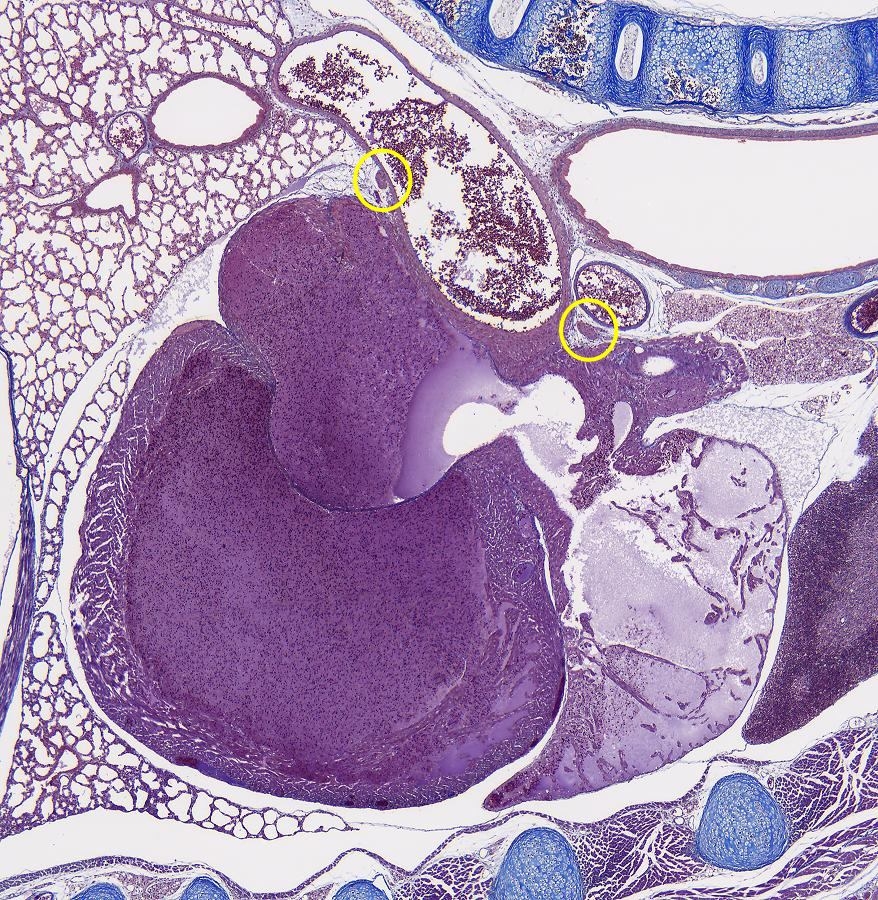

Zum Maus ist es nur ein kleinen Schritt. Hier ein ubersicht. Das Herz zeigt sich Linksunten.

Ubersichtsbild vom Herz. Die zwei Regionen befinden sich in die Gelben Kreisen.